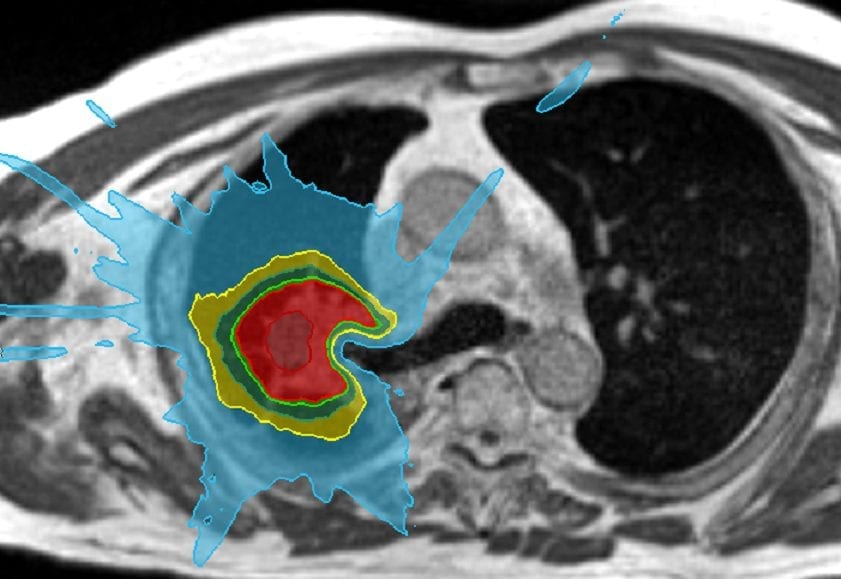

GenesisCare commenced treatment using the very first MRIdian MR-linac in the UK in December 2019 and has subsequently treated over 50 patients in the first 5 months. Using this remarkable system, our team of highly trained MR linac expert oncologists including Consultant Clinical Oncologist, Dr. Veni Ezhil, has now become the first to successfully treat a central lung tumour. The patient a 72 year old male, received eight treatments delivered on alternate days. Daily on-table adaptation helped to sculpt the dose to the proximal bronchial tree and great vessels to keep them well within tolerance while delivering a high dose to the tumour.

Figure 1- Proximal bronchial tree sparing using daily adaptation